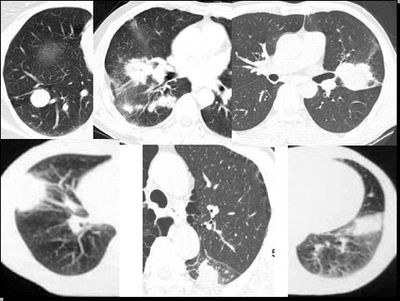

(1)发生部位:炎性假瘤可发生在两肺的任何部位,但多位于肺的表浅部位,邻近胸膜处或者靠近叶间裂。可以跨叶生长,原因可能是跨叶浸润的炎症使得假瘤跨叶融合的结果。

(2)假瘤形态:炎性假瘤的形态不一,可呈圆形.椭圆形或类圆形,也可呈驼峰状或不规则图形。

(3)假瘤大小:多数假瘤的直径在2-4cm,也可大于5cm,少数甚至大于10cm.

(4)假瘤密度:炎性假瘤一般为中等密度,密度均匀。而脓性炎症形成的假瘤则有时可见小空洞。空洞可以单发也可多发。少数瘤体切开时可见脓性物。

(5)假瘤边缘:

①有假无假性包膜者边缘清楚。有的由于肿块不规则可表现分叶状。

② 无假性包膜者,假瘤周围有纤维化和多种细胞成分侵润,表现为片状、边缘模糊的团块状影。或有轻度的渗出性病变,边缘模糊,以组织细胞围增生型多见。有的假瘤周围还可以出现类似周围型肺癌的放射冠状表现。

(6)邻近改变:位于肺周边部的假瘤,其邻近胸膜可见局限性粘连增厚。位于近肺门区的假瘤,偶可阻塞支气管,形成肺叶不张而将假瘤包裹,甚似中央性肺癌,但不出现肺门或纵膈淋巴结肿大。